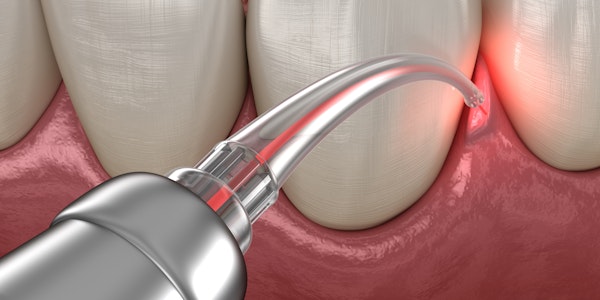

LANAP, or Laser-Assisted New Attachment Procedure, is an FDA-cleared treatment for periodontal disease . Using laser technology, Dr. Thiago Morelli can eliminate diseased tissue and stimulate your body’s natural healing response to regenerate new gum and bone tissue. The procedure also encourages your gum tissue to reattach to your teeth, providing healthy support.

Our periodontists use the PerioLase™ MVP-7™ laser for this remarkable procedure; no scalpel or sutures are required.

- Place Laser: The PerioLase laser fiber, which is about the size of three human hairs, will be gently placed between the gum and the tooth.

- Eliminate Infection: The laser will eliminate the diseased tissue and harmful bacteria in the periodontal pockets.